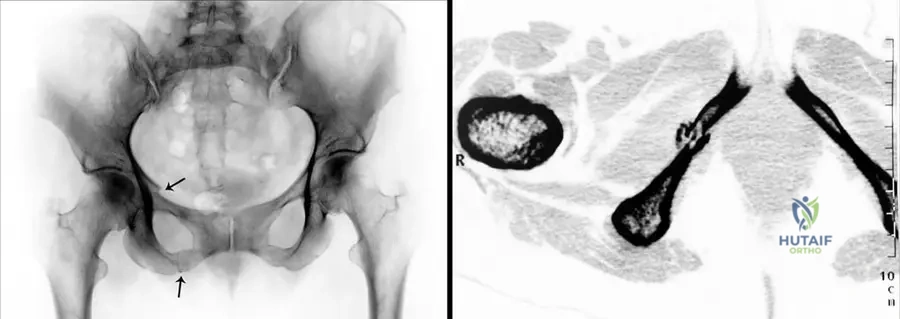

A genetic counselor is discussing the prognosis and recurrence risk for a couple whose child has a form of mesomelic dwarfism. The child presents with hip dislocation, clubhand, and short malformed fingers, and genetic testing reveals an autosomal recessive inheritance pattern.

View Answer & Explanation

Correct Answer: D

Rationale: The text describes Acro–coxo–mesomelic dwarfism as "autosomal recessive dwarfi sm, with hip dislocation, clubhand and foot, short malformed fi ngers, reduced articular mobility of elbows, clinodactyly, brachyrhizophalangia." This matches the clinical picture and inheritance pattern in the vignette. Nievergelt's and Langer types are autosomal dominant.

Question 38

A 3-year-old girl is diagnosed with a mesomelic dwarfism. Her parents are concerned about potential hip problems. On examination, she has short, malformed fingers and reduced elbow mobility. Radiographs show bilateral hip dislocations.

Rationale: The text specifically lists "hip dislocation" as a feature of Acro–coxo–mesomelic dwarfism, which is distinct from the features listed for Nievergelt and Langer type. While "reduced articular mobility of elbows" is mentioned for Acro-coxo-mesomelic, "deformities of the elbow joints" is listed for Nievergelt/Langer, making hip dislocation a clearer distinguishing feature.